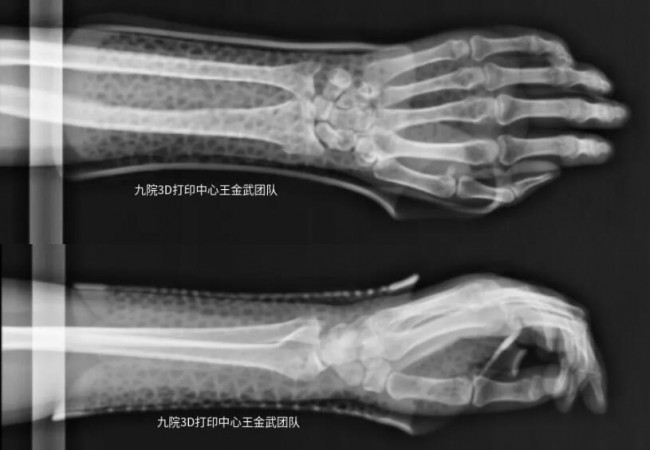

患者左臂桡骨远端骨折,骨折固定后佩戴3D打印固定支具辅助恢复情况良好。

▲佩戴3D打印固定支具拍摄X光片